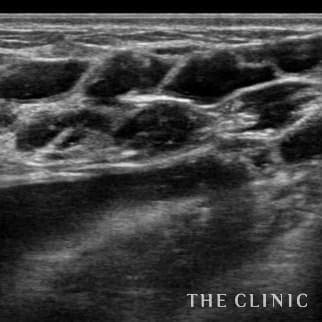

乳腺専用エコーを導入

術前後にエコー検査を行い、手術計画や結果についてを専門的に判断します。